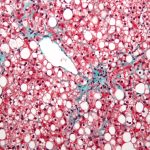

Researchers uncover genetic marker associated with fatty liver disease

The link between a specific genetic marker and severity of non-alcoholic fatty liver disease (NAFLD) has been validated in this study by researchers from several institutions and organisations, including the […]